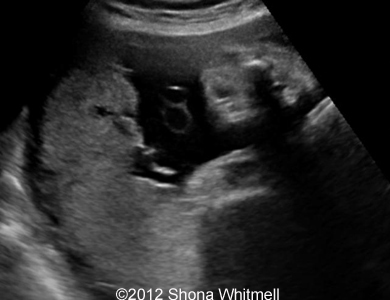

Figure 3, 4: 2-vessel umbilical cord on the placental end.

Image-16

Image-19